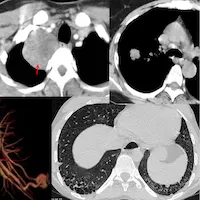

CT Chest Review

Regular reviews of CT chests with cases, snippets and lectures